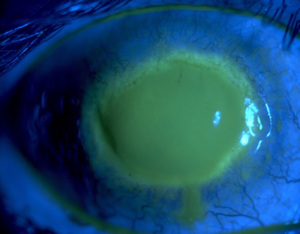

| Fluorescein observation of an eye with Acanthamoeba keratitis | |